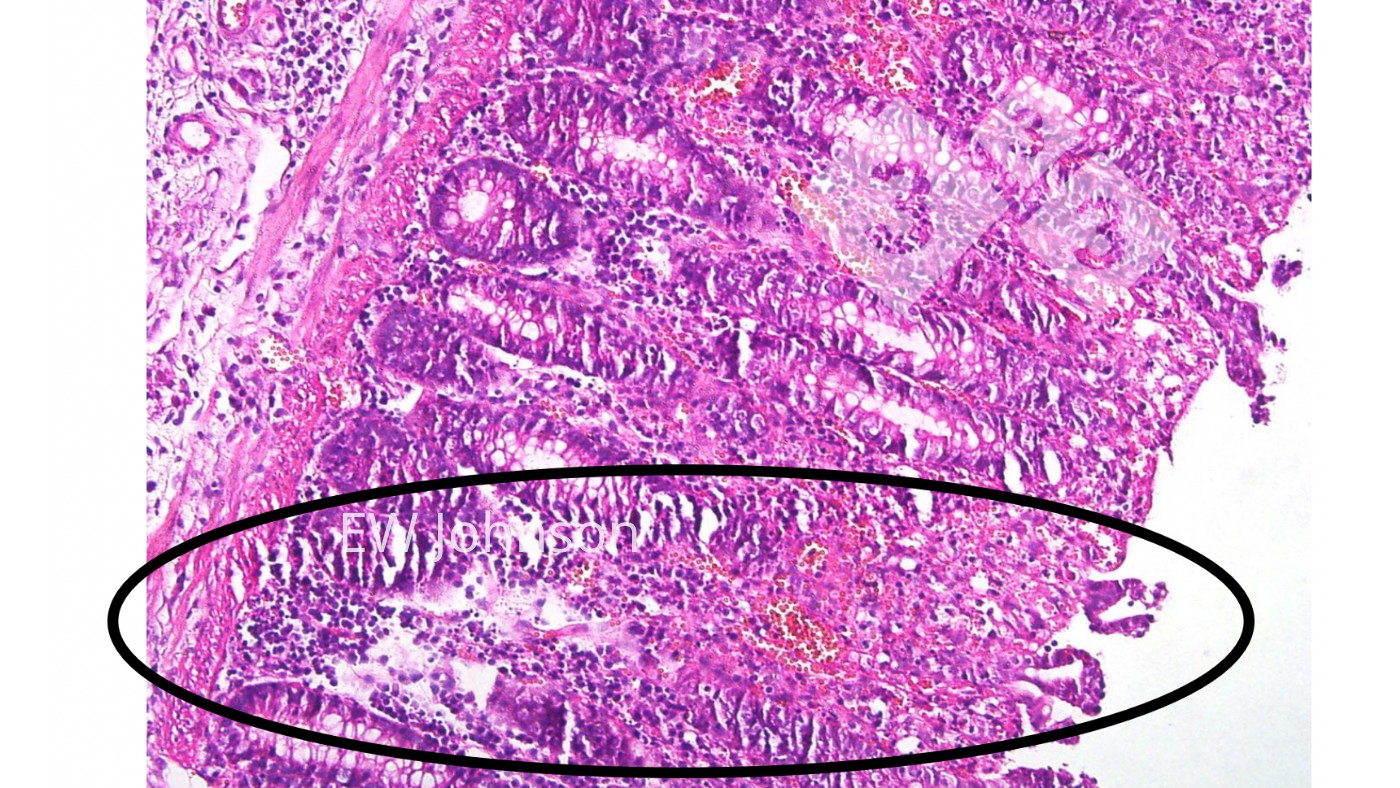

L'examen histopathologique montre une vasculite généralisée avec infarctus, hémorragie et thrombose dans de multiples organes, en particulier le poumon, la rate, les ganglions lymphatiques, les reins, le cerveau et l'intestin. On observe une destruction lymphoïde massive dans les ganglions lymphatiques et la rate, ainsi qu'une vacuolisation des macrophages alvéolaires. La nécrose et l'ulcération de l'épithélium du côlon sont fréquentes (photo 4).

L'utilisation de l'histopathologie pour vérifier les lésions chroniques typiques du vaccin à gènes délétés peut être très utile. Les porcs qui ont reçu de tels vaccins contre la peste porcine africaine présentent souvent des lésions vasculaires chroniques actives, fibrosantes et cicatrisantes, y compris des thrombus et des infarctus dans l'intestin, le foie, les tissus lymphoïdes, le cœur et les reins. Les ganglions lymphatiques peuvent présenter des zones hémorragiques avec nécrose et destruction des lymphocytes et des zones avec fibrose et cicatrisation. Les reproducteurs vaccinés peuvent présenter de larges zones de nécrose et de fibrose pulmonaires souvent confondues avec l'App chronique. Le virus du vaccin peut ne pas tuer le porc, mais celui-ci ne peut souvent pas excréter le virus du vaccin.